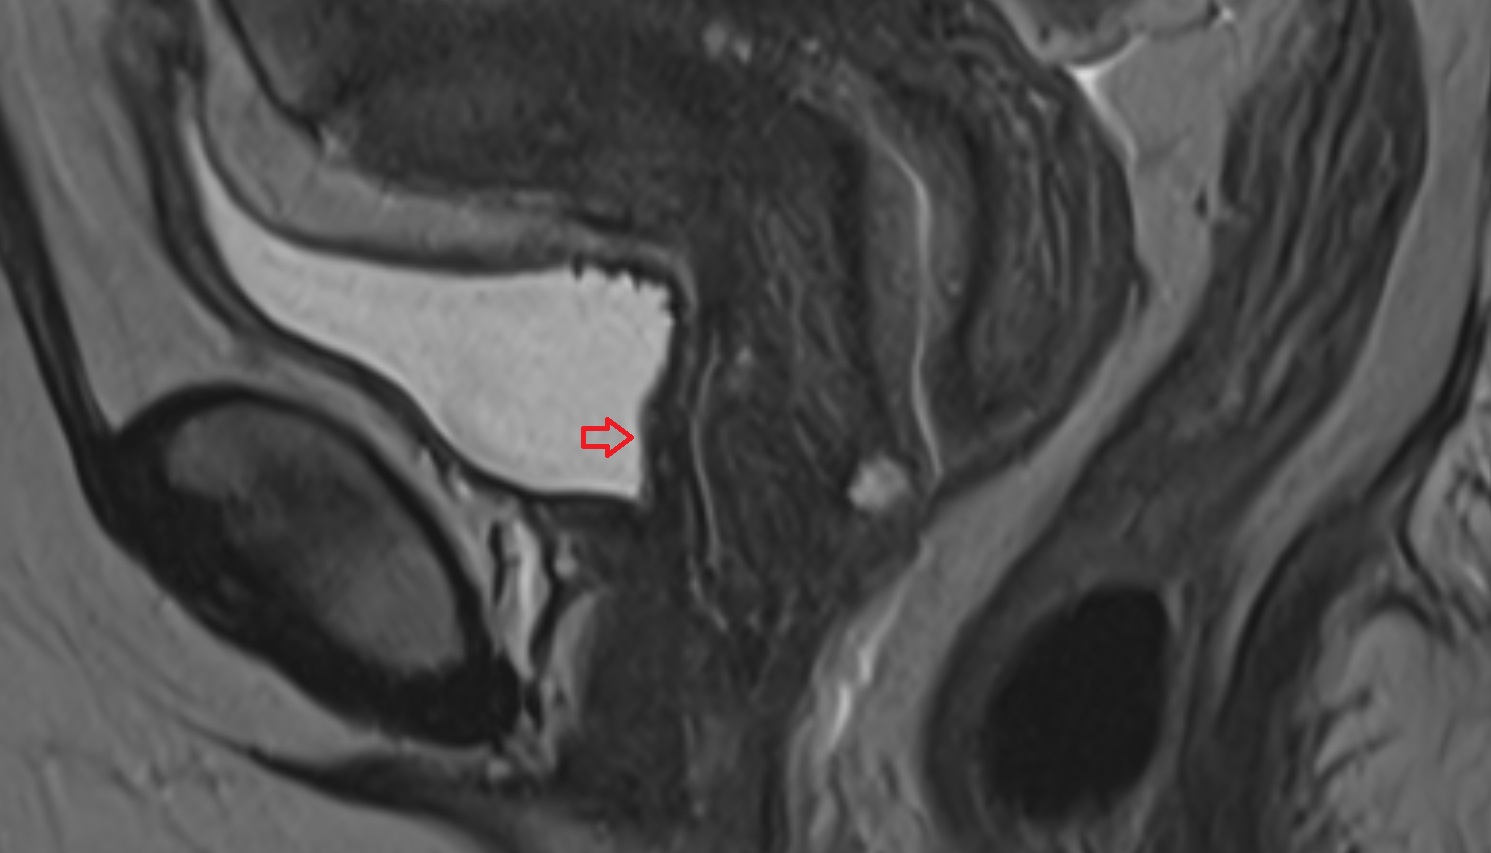

- Uterus

- Body of uterus

- Fundus of uterus

- Cervix of uterus

- Isthmus of uterus

- Vagina

- Fornix of the vagina

- Endometrium of uterus

- Myometrium of uterus

- Perimetrium of uterus

- Junctional zone of uterus

- Vesicouterine pouch

- Rectouterine pouch (pouch of Douglas)